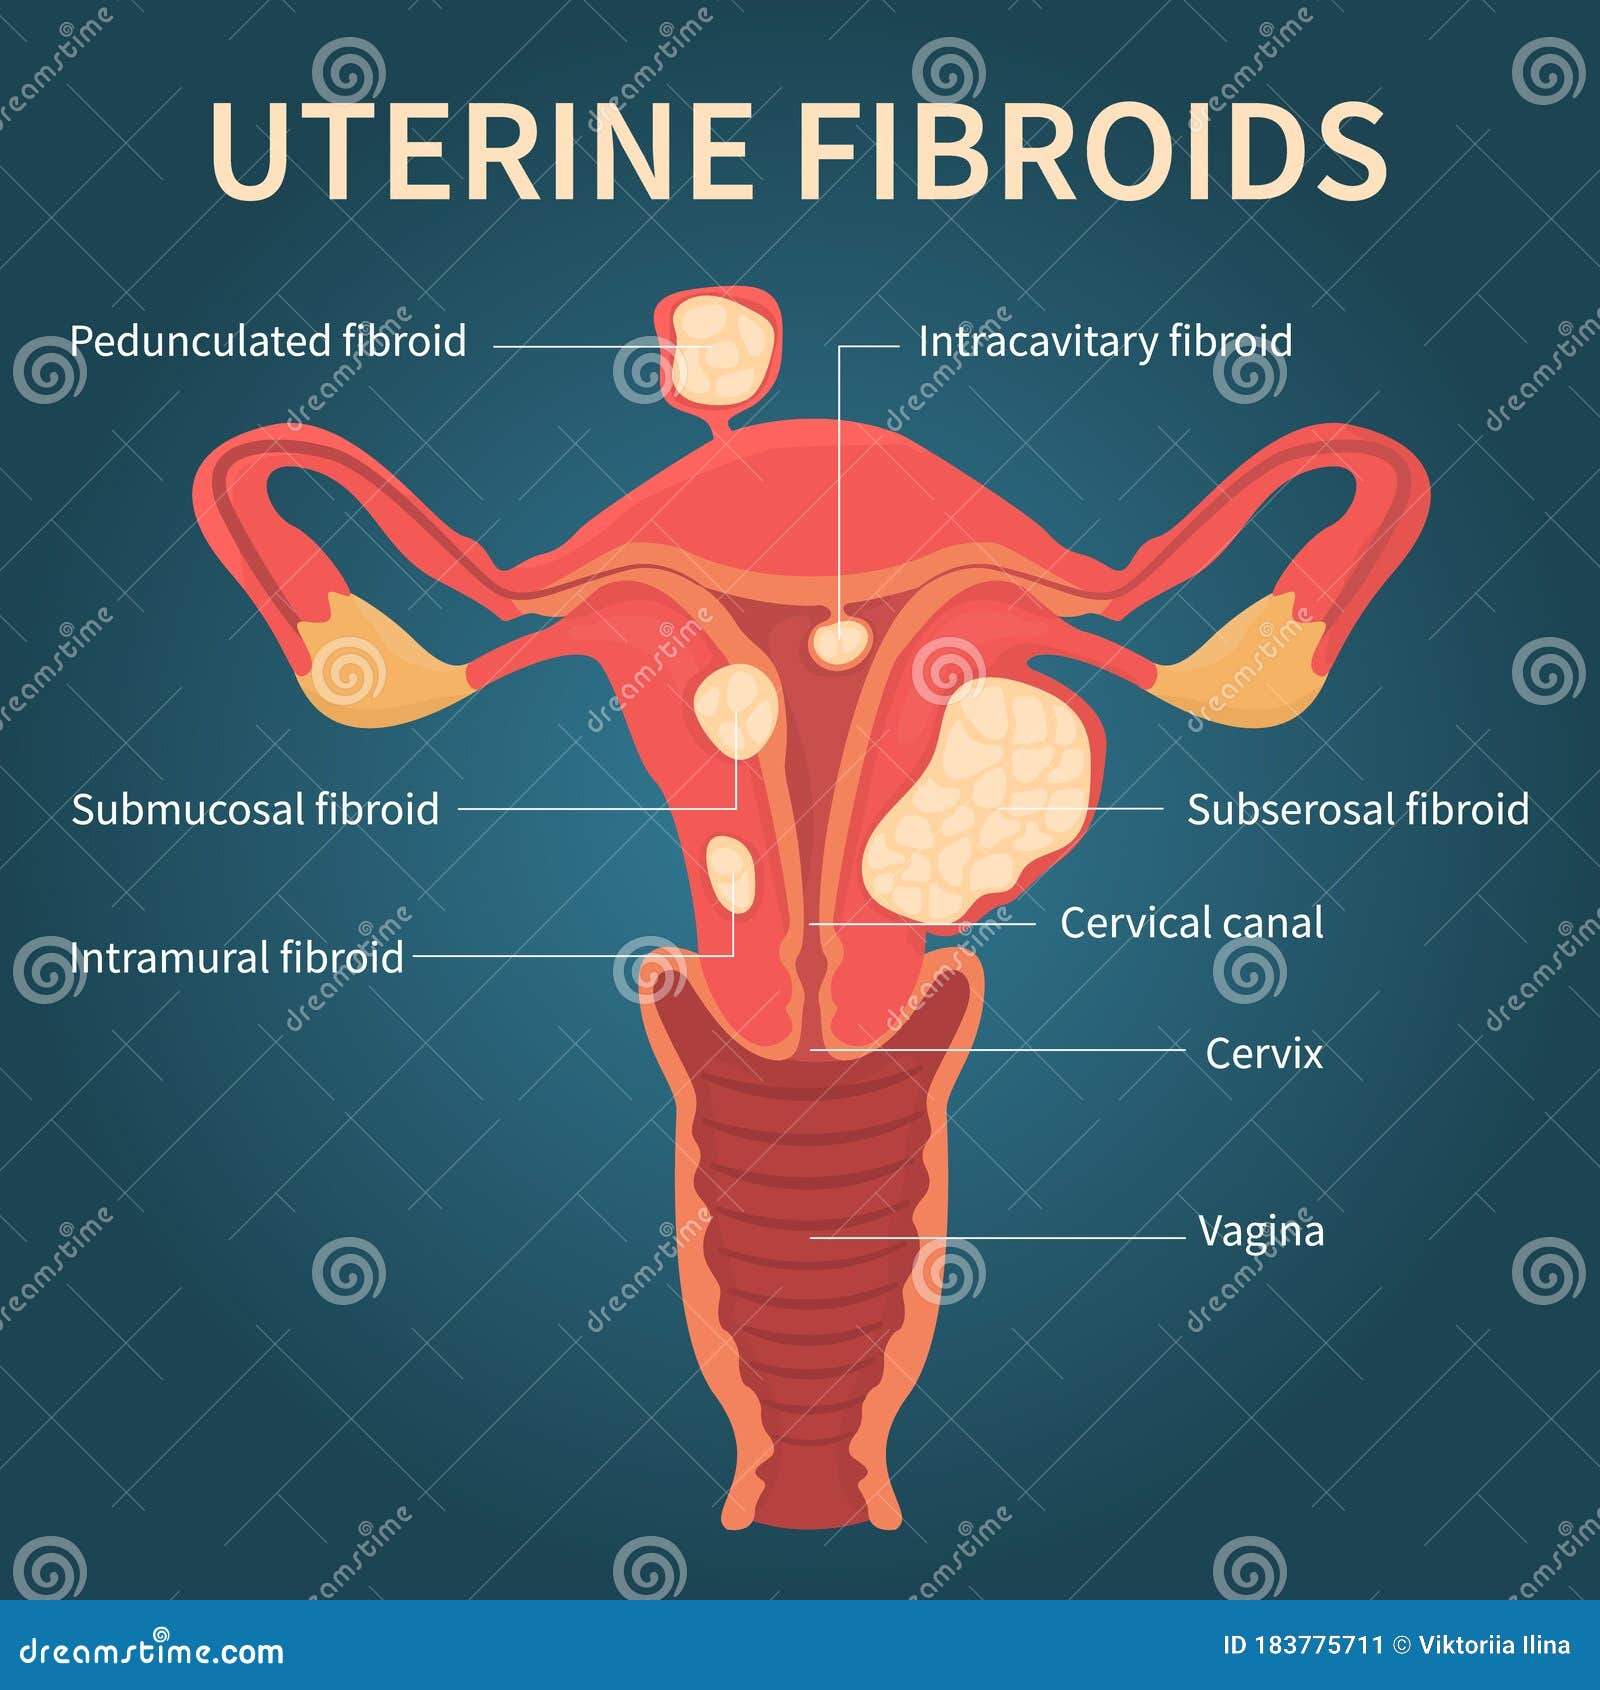

Types of Uterine Fibroids – Dr Pamela Tan | Uterine fibroids, Fibroids …

Types of Fibroid’s? | Fibroids, Hospital, Intramural

Uterine Fibroids Close-up View on Dark Blue Stock Vector – Illustration …

Uterine fibroids. Fibroid types and uterine fibroids treatment | MED Expert